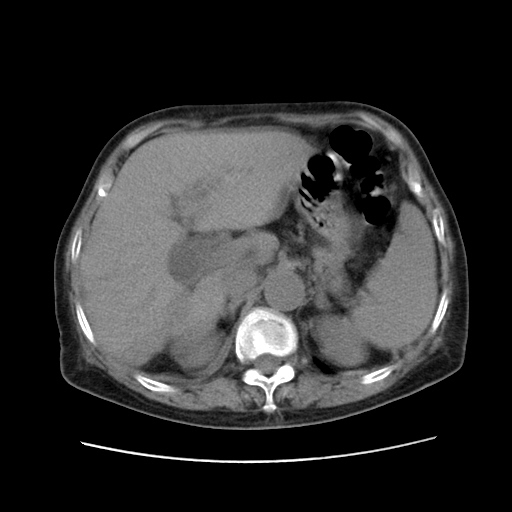

标题: CT25203:上腹部增强,看看

女,77.无不适

胆管扩张,壶腹部占位?

肝脏变异、异位胆囊,肝右叶肝内胆管结石并肝内胆管扩张。

肝内胆管扩张,胆囊炎,胆囊窝积液。 右侧胸腔少量积液。

肝右叶肝内胆管结石并肝内胆管扩张。

肝右叶肝内胆管结石并肝内胆管扩张。胆总管下段梗阻,考虑壶腹部占位。

右侧肝内胆管局限性扩张,其内密度不均匀,扩张的胆管壁增厚,考虑肝内胆管炎合并结石可能性大

肝右叶肝内胆管结石并肝内胆管扩张。胆总管下段梗阻,考虑壶腹部占位。支持